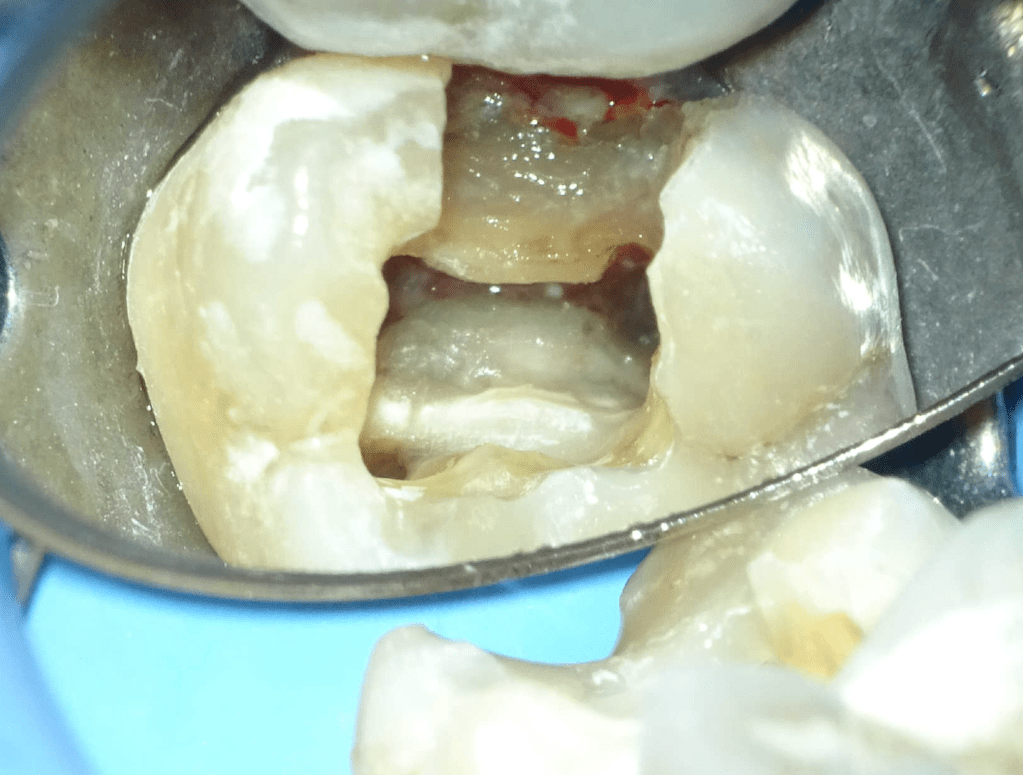

Reconstrucción preendodóntica

Reco preendo + 4 conductos molar superior